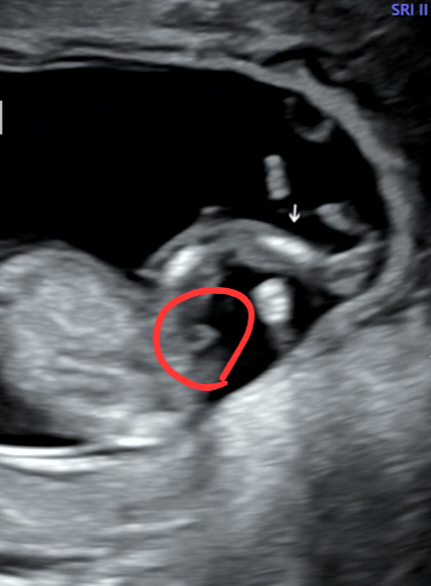

13주차 0일 초음파

아기 옆모습이에요. 저기 보이는게 꼬리일까요 아니면 고추일까요? 남아라고 생각해도 될련지요..^^ 13주차 0일 초음파에요. 모양이 어찌 생겨서 발달하는지 몰라서 궁금해서 여쭤보아요.ㅎㅎ

13주면 여아도 튀어나와있다~~그러는데 제 딸랑구는 12주때부터 매끈했던거 보면 남아일거 같아용! 그래도 너무 확신하지는 마시고 16주 이후까지 지켜보셔요! 진짜 20주 넘어서 바뀌시는분들도 있더라구요🫢